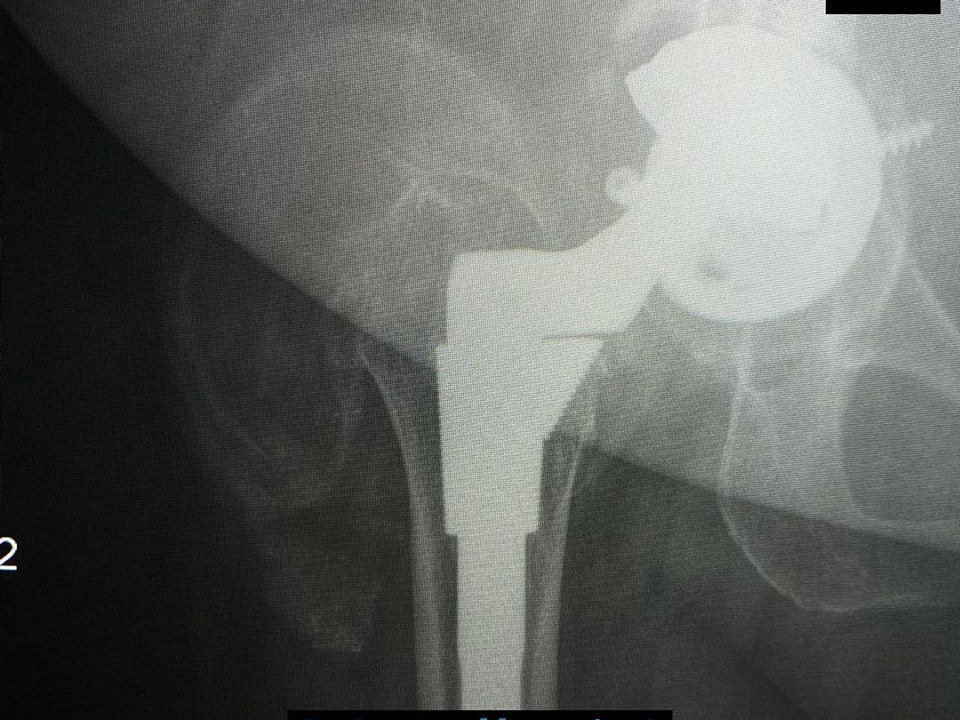

Metallosis